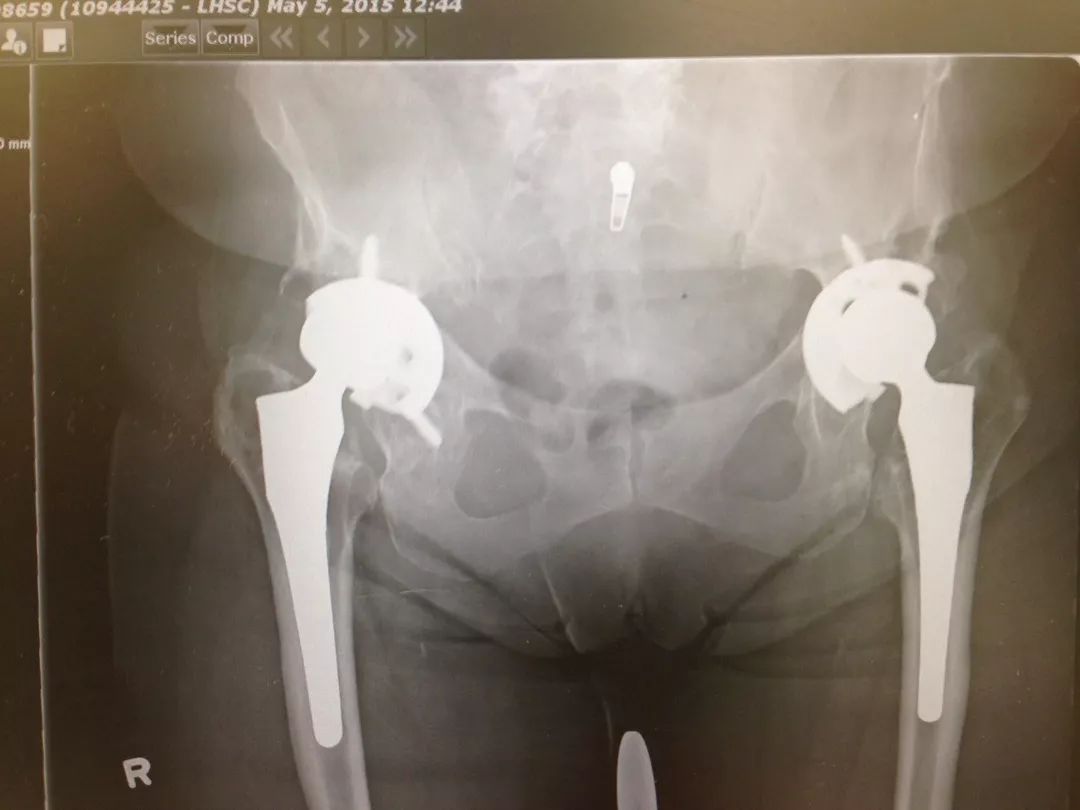

图2各种原因所致人工髋关节假体失败,需要行髋关节翻修术

55岁,女性患者,8年前于外院行右侧全髋关节置换术,术后恢复良好;2年前开始出现右髋疼痛,下蹲困难,行走后疼痛明显。门诊以“右髋关节假体松动”收入院。

术前X线片示右侧全髋关节置换术后,假体柄周围见透亮影,考虑假体柄松动

右髋翻修术后髋关节假体稳定,假体位置角度良好,可早期下地活动锻炼